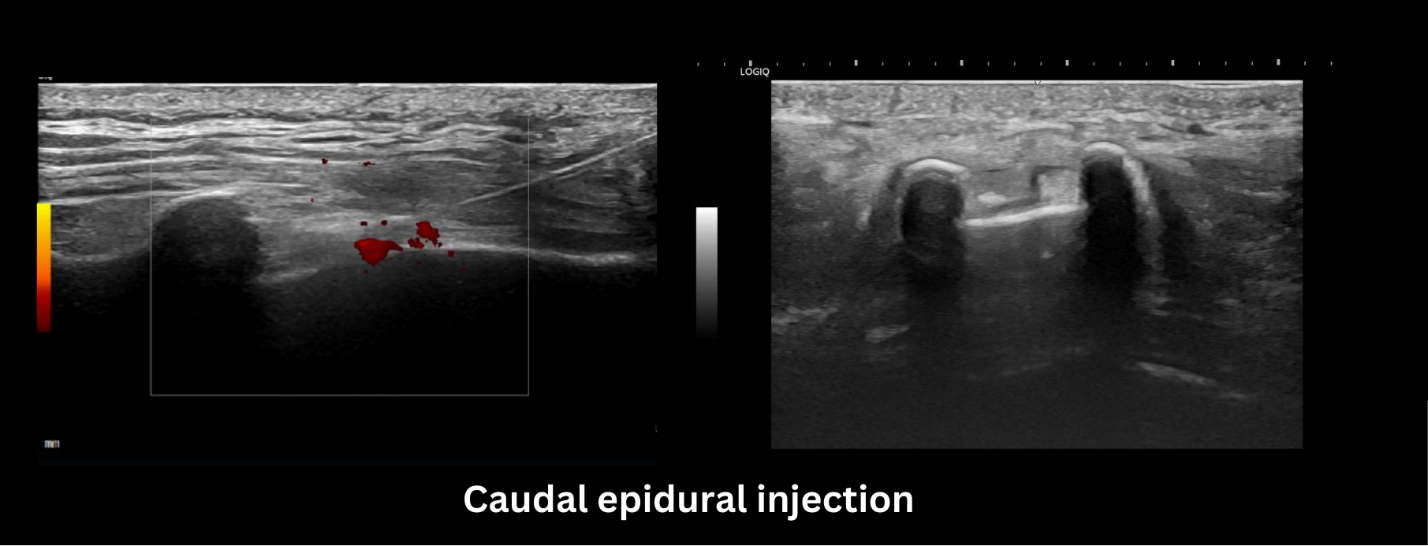

ปัจจุบันได้นำเครื่องอัลตราซาวด์มาใช้ในการระบุตำแหน่งในการฉีดยาเข้าไปที่โพรงไขสันหลังเพื่อเพิ่มความแม่นยำ ลดอัตราการฉีดยาผิดตำแหน่ง และลดความเสี่ยงในการรับรังสีเอ็กซ์ในผู้ป่วย ทำให้การฉีดยามีประสิทธิภาพและปลอดภัยมากยิ่งขึ้น แต่อย่างไรก็ตามก็จะยังมีความเสี่ยงที่อาจเกิดขึ้นได้ เช่น ภาวะติดเชื้อ เลือดออก ดังนั้นควรทำภายใต้อุปกรณ์ที่สะอาด ปราศจากเชื้อ เทคนิคที่ถูกต้อง เพื่อลดภาวะแทรกซ้อนที่อาจเกิดขึ้น

ดังนั้นการฉีดสารละลายกลูโคสเข้าโพรงไขสันหลังภายใต้การใช้อัลตราซาวน์นำทางจึงเป็นตัวเลือกหนึ่งของผู้ป่วยที่มีอาการปวดหลังเรื้อรังที่ทำกายภาพบำบัดมาแล้วอาการปวดยังไม่ตอบสนองเท่าที่ควร

ภาพแสดงการฉีดสารละลายเข้าไปที่โพรงไขสันหลังภายใต้การใช้อัลตราซาวด์นำทาง